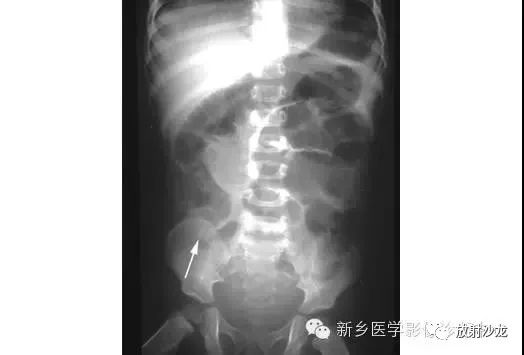

上图腹部平片检查是一6岁男孩,出现呕吐和急性右髂窝疼痛进行的。两个关键的发现在哪里?(提示:通过放射科医生所提供的箭头可以缩小关注点。)

右髂窝多个扩张的小肠襻出现小的钙化结节。小肠袢可与大肠区分开来,因为小肠的环状襞延伸至整个肠壁,而结肠袋只是部分延伸存在。在右下腹(箭头)的钙化结节高度提示阑尾粘连。这个病人开腹手术发现阑尾粘连致小肠梗阻。